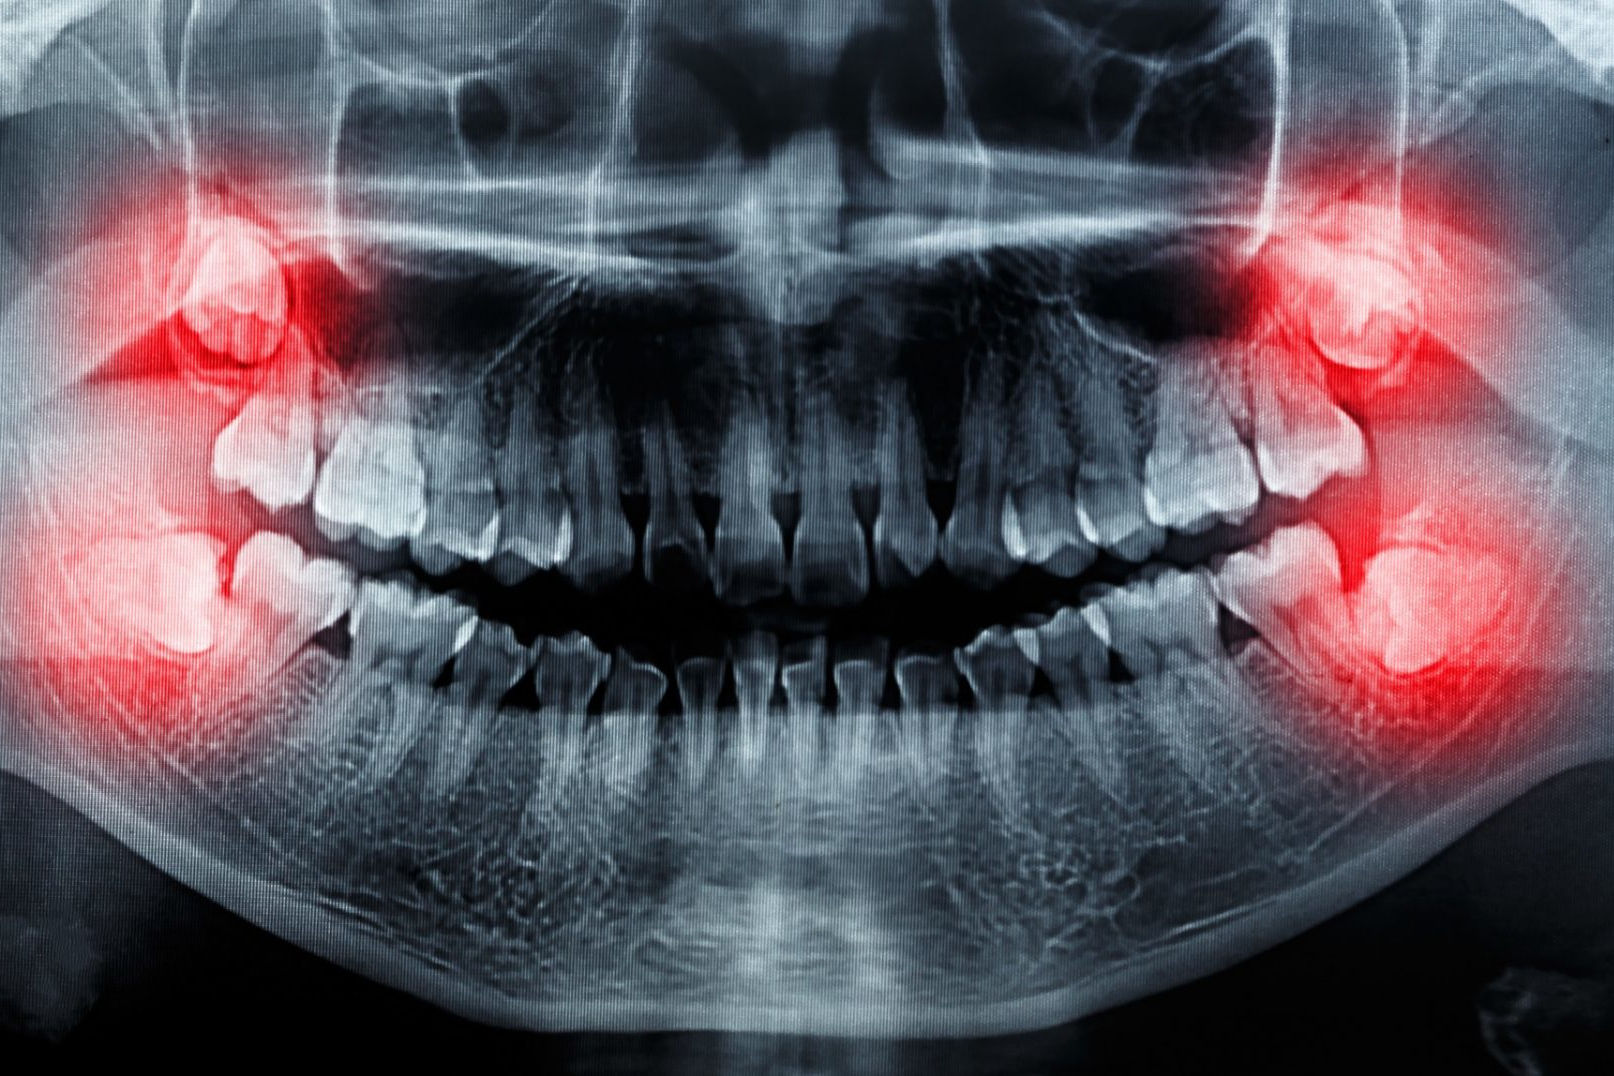

Surgical extractions – removal of wisdom teeth

Wisdom teeth are usually firmly anchored, have 3-4 roots, and require surgical treatment to be removed. Furthermore, we often find that wisdom teeth grow inwards, are deeply imbeded in the jawbone and their position usually deviates from the normal. The reason behind it is that the facial skeleton, especially the jaw, has become smaller over the millennia, leaving less space for the same number of teeth. It is becoming increasingly common for wisdom teeth not to form at all.

If a wisdom tooth cannot grow out completely and remains partly under the gum, it can become inflamed. Cleaning these teeth can also be complicated, which can cause additional inflammation, even under the palate. This can cause pain, tooth decay, and bad breath.